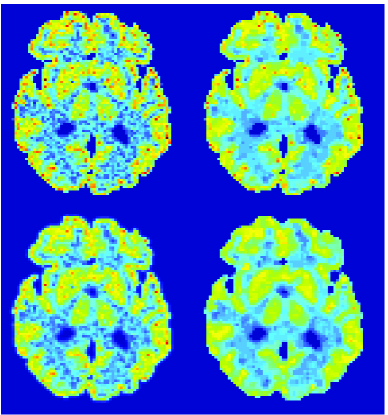

In the images shown in the figures we illustrate the calculated uptake rates of the FDG. Images for the CMRGlc can be obtained by directly scaling . In figure 1 we compare the result of using Patlak and TV-Patlak for estimating the uptake rates with respect to no noise, noise in the input function, Poisson noise in the sinogram, and finally with respect to the case in which the irreversibility assumption is violated but without noise in the sinogram or input data. In each case the histogram of the relative errors is given on the left, the Patlak image in the middle and the TV-Patlak on the right. The different scales in the histograms are due to the total number of results illustrated. When there is no noise (triples and ) the histogram illustrates results over all voxels but only one simulation, while for the noisy simulations the results are for all voxels over all realizations of the noise. The TV-Patlak images are more homogeneous in all cases and the relative errors are smaller. The figures clearly show the improvements of employing the TV-Patlak method as compared to using Patlak independently for each voxel. This is confirmed in figure 2 in which images with noise in the sinogram, positive and different noise levels in the input function are shown.

In figures 3 and 4 we illustrate the uptake rates and relative error in the uptake rates, respectively, calculated by Patlak, TV-Patlak, Patlak-GF and Patlak-MF for one simulated data case , i.e. , noise in the input function and Poisson noise in the sinograms. The uptake rate image generated by Patlak-MF is visually smoother than that by TV-Patlak, but the equivalent histograms show that the relative error is higher for Patlak-MF than for TV-Patlak; the Patlak-MF image is over-smoothed.